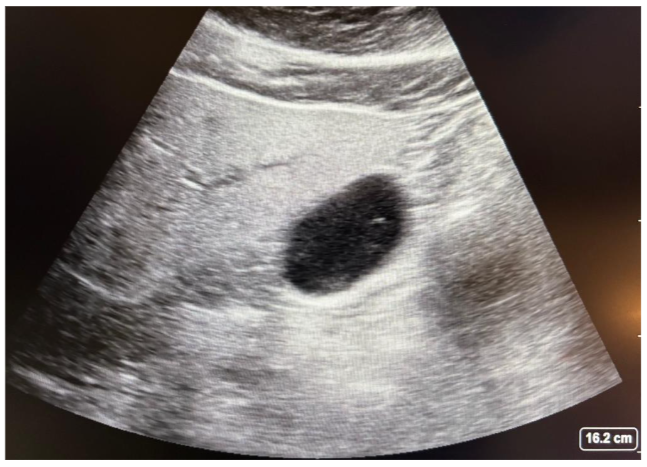

There are some important limitations to consider when performing gastric POCUS in patients with hip and femur fractures. Specifically, it is imperative to confirm that the stomach is empty; it is important to assess the gastric contents in the right lateral decubitus position which may not be feasible in patients with a hip or femur fracture. The rationale is that in the right lateral decubitus position, gastric contents will displace to the atrium. This is the reason why an assessment in the supine position cannot determine if a patient has an empty stomach. Any time solid contents are visualized (frosted glass pattern), the patient is considered to have a high aspiration risk. This same applies to high volume aspiration, as shown in figure 2. In this situation, the anesthesiologist has to evaluate the patient for deep sedation or placing a supraglottic device.